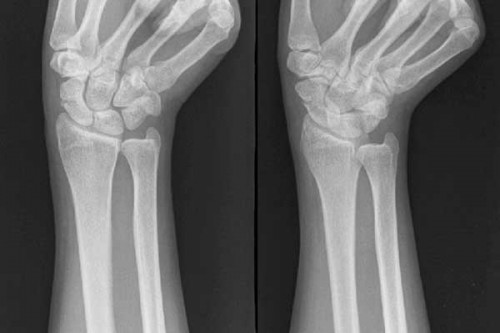

骨折手术治疗最佳时机是什么时候?广东药学院附属第三医院骨科专家介绍,骨折后最好手术的治疗时机取决于多种的因素,手术可分为三类的:急症手术、限期手术和择期手术的。那么骨折手术治疗最佳时机是什么时候? 一、急症手术:需要急症的处理的损伤包括开放

骨折患处到什么时候才能愈合?广东药学院附属第三医院骨科专家指出,骨折不愈合这是很常见的现象,也意味着在修复的过程中已经终止了,X线片上可见骨断端骨质硬化,髓腔封闭。临床士骨折处有异常活动(假关节活动)。那么,骨折长时间不愈合怎么办呢?接下来